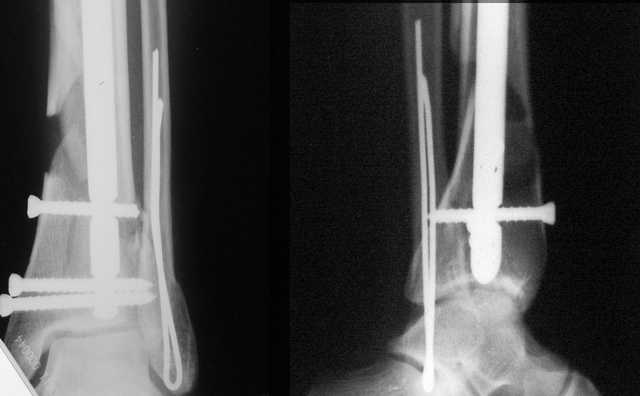

Dear all,40 y.o. man had sustained this terrible fracture falling from a motorbike.

Closed fracture.

We have put his limb in traction.

After some days of traction I would like to insert an external fixator (I think a circular one instead of a monoaxial one, because of the multiplanar situation of the fracture).

This is really Pilon Fx (C3.3; the high energy and the extent of distal tibia comminution are defining it).